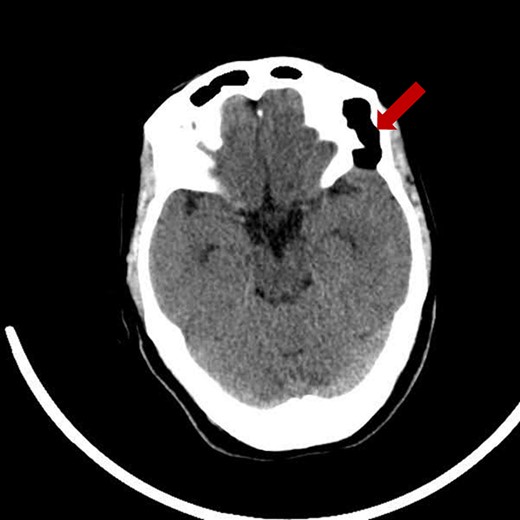

Prior diagnostic imaging included a computed tomography (CT) scan, revealing a hypodense lesion in the left fronto-zygomatic region (Fig. 1). Subsequent brain magnetic resonance imaging (MRI) showed a high-intensity lesion on T1-weighted images (T1WI) (Fig. 2A), and an iso-to-hyperintense lesion on T2-weighted images (T2WI) (Fig. 2B).

Pre-operative brain MRI exhibiting: (A) a high-intensity lesion in the left fronto-zygomatic region on coronal T1-weighted images (T1WI), and (B) Axial T2-weighted images (T2WI) depicting variable signal intensity ranging from iso- to hyperintense.